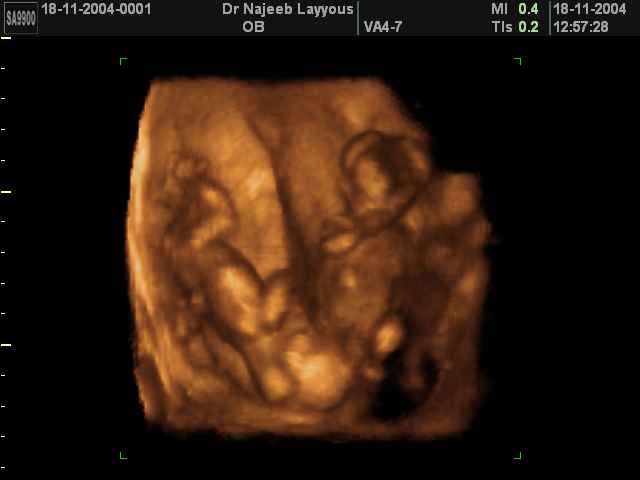

- 3D Photos échographie de grossesse multiple

3D Photos échographie de grossesse multiple : Jumeaux, triplés et quadruples| Dr N Layyous